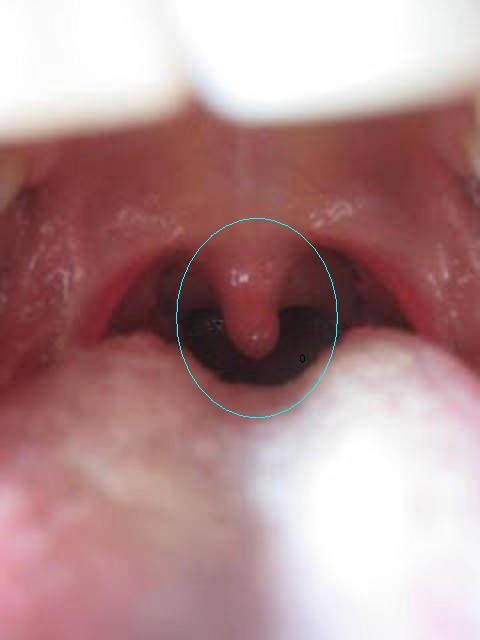

تقوم اللهاة باغلاق الممر التنفسي الموجود في الحلق بحيث لا يدخل الطعام الى الأنف.

اصابة الانسان بالجفاف يؤدي الى تضخم اللهاة وتورمها، وقد يصل حجمها الى 5 اضعاف حجمها الطبيعي، وعند تضخمها وملامستها اللسان او اسفل الحلق تسبب احساسا مزعجا ومشكلة في الاكل والشرب والتنفس.

كما لوحظ أن الاشخاص الذين لديهم لهاة طويلة يصابون بانقطاع التنفس اثناء النوم، وفي بعض الحالات الشديدة قد يتم استئصالها كليا او جزئيا.